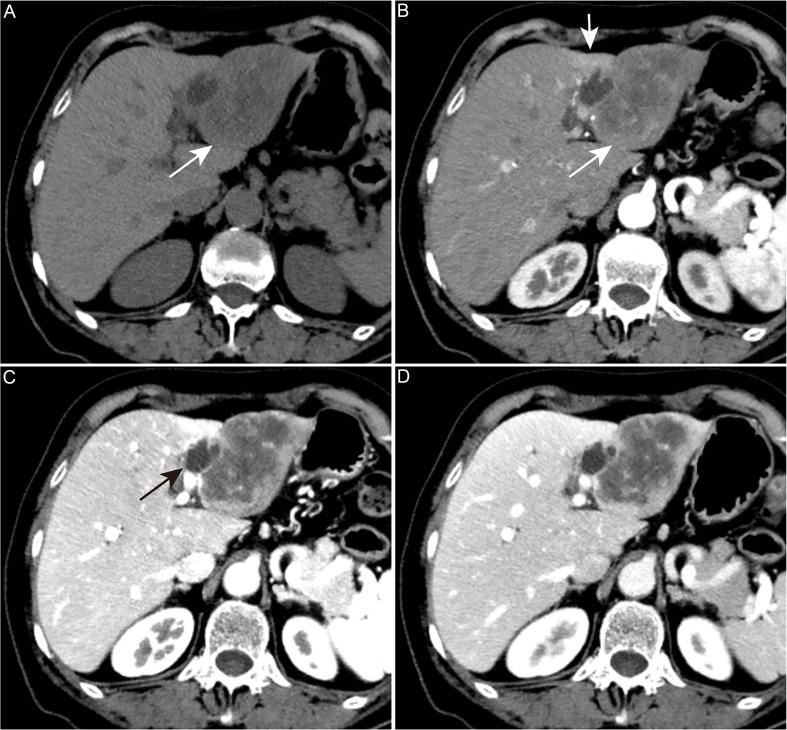

肝内胆管癌的分子和组织学特征及相关影像学特征

Molecular and Histological Profiles and Relevant Imaging Signatures of Intrahepatic Cholangiocarcinoma.

Intrahepatic cholangiocarcinoma (iCCA) is the second most prevalent primary liver cancer, characterized by insidious onset and high malignancy. Many patients are diagnosed at an inoperable stage, and the effectiveness of chemotherapy and radiotherapy remains limited. This study aimed to provide a comprehensive review of the histological classification, genetic alterations, molecular subtypes, and corresponding imaging signatures of iCCA, highlighting its heterogeneity and offering insights into targeted therapy and personalized treatment. The heterogeneity of iCCA poses significant challenges to both targeted therapy and immunotherapy, necessitating in-depth exploration at the molecular and subtyping levels. Investigating genetic variations, signaling pathway alterations, and molecular subtypes can aid in patient stratification. Stratifying iCCA patients allows for more precise treatment selection, ultimately improving survival outcomes. Imaging, as a non-invasive tool, holds substantial potential for predicting subtypes and molecular profiles. It is possible to infer histological and molecular features from imaging, or to interpret imaging signatures in light of known histological and molecular data. This integrative approach, combining external imaging with internal molecular insights, fosters a comprehensive understanding of iCCA's characteristics and enhances clinical management.

摘要